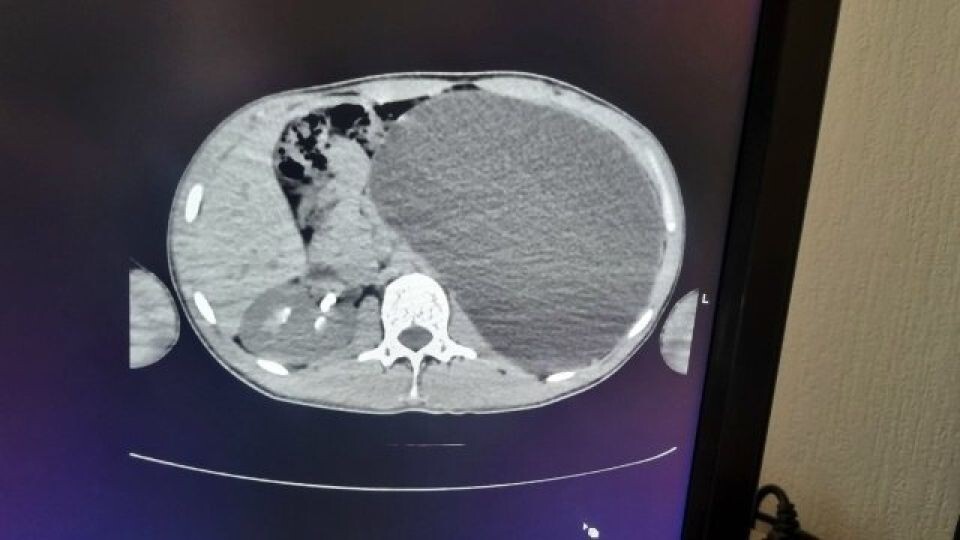

В Новосибирске плановое медицинское обследование перед трудоустройством фактически спасло жизнь 17-летнему юноше. Во время ультразвукового исследования врачи обнаружили у него выраженный гидронефроз — патологическое расширение почки, вызванное накоплением жидкости, сообщает Минздрав Новосибирской области.

До обследования подросток не испытывал боли и не высказывал жалоб на самочувствие. Он считал себя полностью здоровым. Однако результаты УЗИ показали серьезную угрозу: почка увеличилась до гигантских размеров.

Как сообщили в ДГКБ № 1, орган достиг объема примерно пятилитровой емкости и занимал значительную часть брюшной полости, сдавливая соседние органы. Врачи назвали ситуацию крайне опасной — любое механическое воздействие могло привести к разрыву и внутреннему кровоизлиянию.